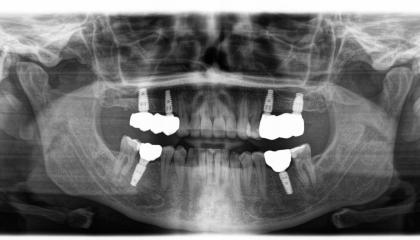

Tooth Replacement

Zirconia bridge on Southern DC Implants

Zirconia Implants